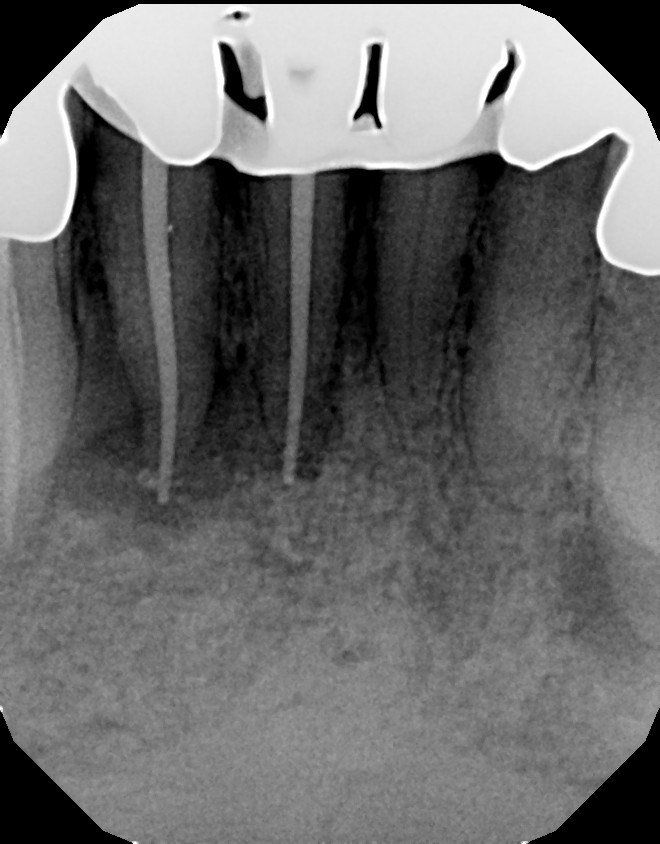

Long Island Endodontist shares his experience with root canal problems.

This is a multiple tooth / root issue that developed over time (4-5 years) under crowns where the nerves died and caused infection. After 3 months, bone regeneration (healing) occurred where infection was initially present. Endodontists (root canal specialists) are an important part of dental care for diagnosing and treating root issues.